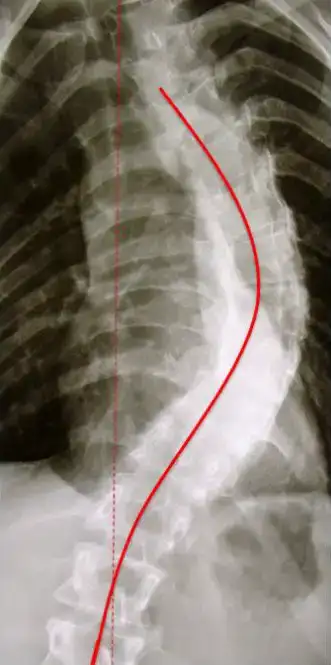

Die degenerative Lumbalskoliose ist eine Verkrümmung der Wirbelsäule in der Frontanebene die entstanden ist durch Abnützung einzelner Bewegungssegmente über mehrere Segmente. Diese Abnützungen führten dann auch zu Instabilitäten.

Eine degenerative Lumbalskoliose entsteht unter Umständen durch einen natürlichen Alterungsprozess durch Abnützung der Bandscheiben, der Gelenke und der sich dadurch ändernden Statik. Eine asymmetrische Abnutzung der Bandscheiben scheint ebenfalls eine Rolle zu spielen bei den Skoliosen. Kommt es zu einer Abnützung in mehreren Lendenwirbeletagen übereinander, entsteht durch die ausgeprägte Instabilität zu einer Seitabweichung der Lendenwirbelsäule und es bildet sich eine skoliotische Deformität aus. Durch die bestehende Instabilität kommt es zum Verlust der Rotationskontrolle der Lendenwirbelsäule, wodurch die physiologische Krümmung der Lendenwirbelsäule (Lordose) aufgehoben wird und das normale Wirbelsäulenprofil im Seitenbild verloren geht.